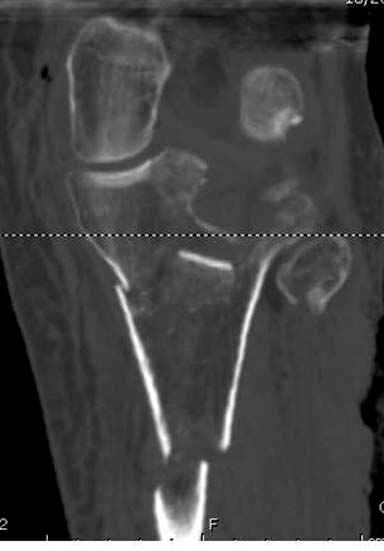

Отдельные переломы тибиал плато и перелом проксимальной трети большеберцовой кости отличаются от переломов тибиал плато с вовлечением диафиза. Здесь перелом тибиал плато типа Schatzker VI, полученный в результате высокоэнергетической травмы. Перелом метафиза образовал отрыв суставной поверхности от диафиза с вовлечением медиального и латерального мыщелков. Двухмыщелковые переломы из-за укрочения опасны развитием компартаментального синдрома, повреждением латерального мениска и связок.

Если там действительная импрессия, пустое место без структуральных заполнителей, кость или синтетические материалы, не восстановится, а образуется коллапс, и ось конечности поведет после нагрузки. Кроме того там возможно "болт стяжка"?, в медиальной стороне выступает за кортекс, можно было укоротить! Потом создается впечатление, что не соответствуют мыщелки большеберцовой и бедренной костей? Покажите снимок.

Ваша упорство с минимальными данными защищаться забавляет, и пока не все убедились в Вашей правоте. Для нормальной защиты необходимы аргументированные доказательства исследованиями. КТ сканы и прицельно сделанные снимки коленного сустава, а так все аргументы - не более чем "моя фиксация, мне нравится". Без этих доказательств пока только Ваше упорство.....

Здесь пару случаев для сравнения,...в первых 1-4 слайдах метод фиксации одним фиксатором, как видно после 8 месяцев сохранилась ось. С 5 по 9 вариант двумя пластинами...